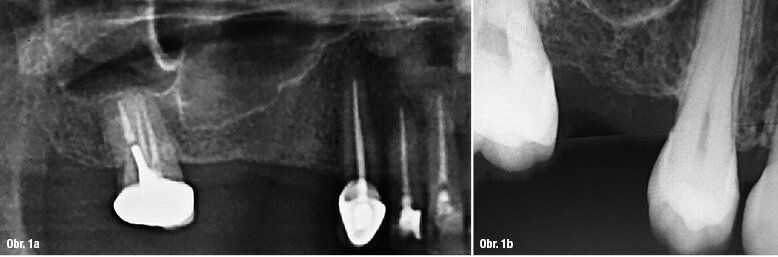

Obr. 1a: RTG snímek bezzubého prostoru znázorňující pneumatizaci čelistní dutiny Obr. 1b: Schéma představující možný klinický vývoj u pacienta a také možnou fluktuaci reziduální výšky alveolárního hřebene. V požadovaném místě implantace, k nahrazení zubu 16, byly naměřeny 4 mm.